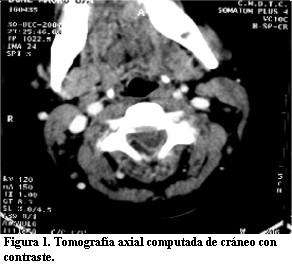

- Tomografía axial computada de cráneo y columna: en el interior del canal raquídeo por fuera del saco dural y lateralizado a derecha, se observa imagen hipodensa que desplaza saco dural hacia la izquierda, de unos 6 cm, localizada a nivel de C2 a C7 (figura 1).